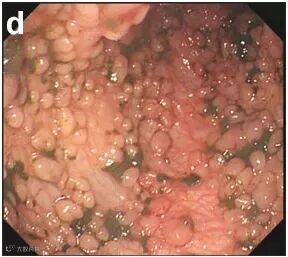

一查竟发现,肠内密密麻麻都是息肉

察觉到孩子的异样后,父母立即带她去医院检查。胃肠镜及CT检查发现小花的结肠壁布满息肉样隆起。

练医生查看完检查结果,详细询问家族史后,考虑为家族性腺瘤性息肉病所致的便血及贫血。

据练医生介绍,小花患上的是一种家族遗传性肠病——家族性腺瘤性息肉病。

这种病,如不预防性切除结肠,患者至50岁时几乎100%癌变。

后者中有一种特殊类型,叫“家族性腺瘤性息肉病”(新闻中的小姑娘就患的这种)。

此类患者具有非常明显的家族史,其祖父、父亲、兄弟等可能接连患上大肠癌。

患者从十几岁开始,肠道就开始长息肉,随着年纪增长,息肉数量越来越多,癌变的可能性也越来越大,需尽早治疗。